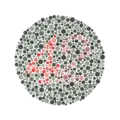

Le test se compose de trente-huit planches colorées, sur lesquelles un cercle constitué de points de différentes tailles et de couleurs légèrement différentes, lesquels sont apparemment disposés de manière aléatoire.

Les modèles de points se différencient par leurs couleurs et par un nombre.

Il permet de détecter toutes les déficiences dichromatiques sauf la tritanopie et la tritanomalie, d’ailleurs très rare. Une planche pseudo-isochromatique est constituée d’une mosaïque de points de couleurs différentes, disposés de façon apparemment aléatoire, au sein duquel apparaît une forme sur un fond. En réalité, les couleurs utilisées sont situées sur des axes de confusion colorés prédéterminés pour mettre en évidence un type de daltonisme précis. On utilise un nombre réduit de teintes. Chacune d’elles apparaît à plusieurs degrés de taille, de saturation et de luminosité. Ces degrés sont identiques pour chacune des couleurs représentées. Un ensemble de points reproduit une forme reconnaissable par l’unité de la teinte, mais, au sein de cette forme, on trouvera plusieurs saturations ou luminosités différentes de façon aléatoire. Le daltonien qui ne verra pas la couleur ne pourra pas non plus déchiffrer la forme par le seul fait d’une homogénéité de saturation ou de luminosité. À l’inverse, il existe des planches dans lesquelles cette homogénéité est utilisée pour faire percevoir des formes à des dichromates alors que les sujets normaux, trompés par des couleurs qui leur paraissent différentes, ne les percevront pas. Dans le daltonisme héréditaire, les lignes de confusion sont nettes et parfaitement déterminées. Cela permet une excellente fiabilité aux planches bien conçues, à la condition que les couleurs soient reproduites à l’impression. En revanche, par construction, une planche pseudo-isochromatique n’est pas adaptable et si l’axe de confusion du dichromate n’est pas rigoureusement celui qui a été prédéterminé, la planche sera jugée défectueuse. Cela se produit le plus souvent dans le cas d’une dyschromatopsie acquise. Chaque groupe de planches (tables) reproduites dans l’annexe (page 27 à 33) doit être interprété différemment.

Exemples de planches représentant successivement les numéros 12, 6, 2 (visible seulement en cas de déficience rouge-vert) et 42.

Ishihara Planche no 1.

Ishihara Planche no 1. Ishihara Planche no 11.